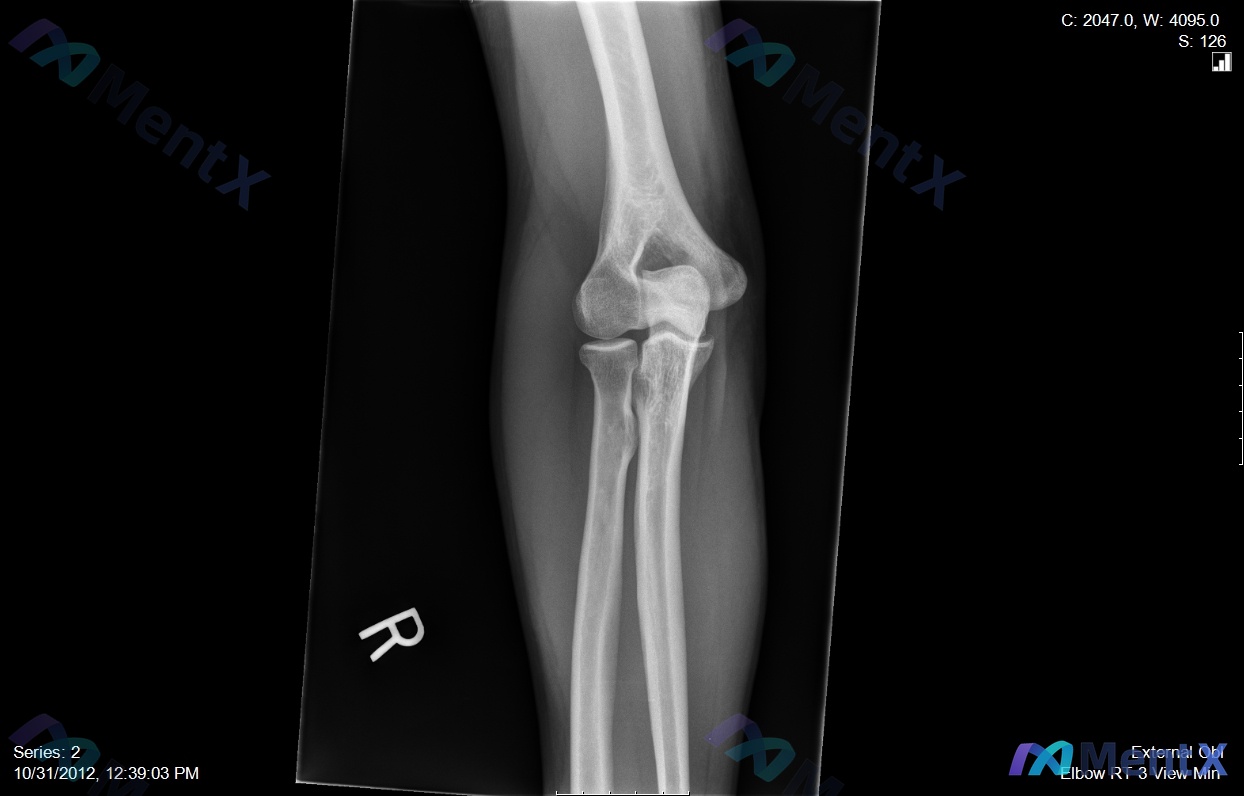

- 右肘X光(正/侧/斜位):肱骨远端、尺桡骨近端皮质连续,关节面平整,关节间隙正常,无骨折/脱位/骨赘/游离体,脂肪垫无抬高。

- 右肘MRI(修正后聚焦):虽然报告张冠李戴,但结合临床,应该重点看肱二头肌腱止点(桡骨粗隆)——预期会有肌腱增粗、T2/PD压脂高信号(水肿/炎症)、纤维部分中断的表现。